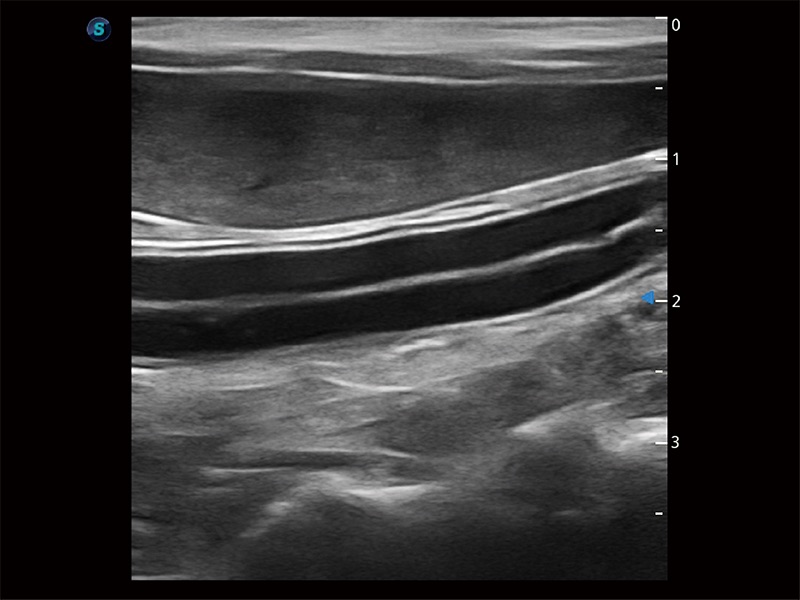

• Micro F 显微血流成像

极大提升超低速微细血流的检出能力,同时更精准地滤除软组织和超声信号,为兽用医生提供以往无法通过常规血流获得的疾病诊断信息。

(犬)肾脏显微血流